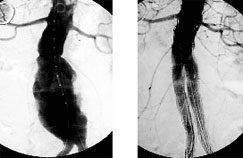

İlk hastamızın stent öncesi ve sonrası anjiografik görünümü.